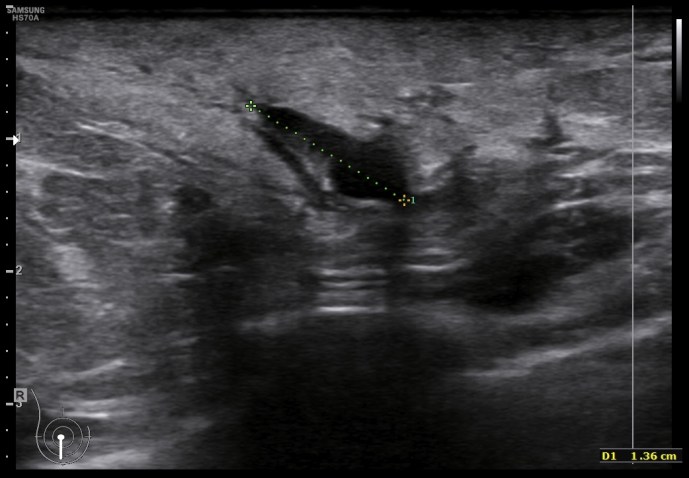

Te presento una mastitis tipo, con un componente de resistencia al antibiótico, con lo que la paciente no mejoraba pese al tratamiento, además presentaba una colección con un tracto que abocaba en la superficie y drenaba líquido purulento a la superficie.

En la imagen 3 puedes ver un absceso, complicación de una mastitis, cuyo aspecto es el de una colección anecoica, que si observas, quieres buscar la superficie de la piel. La imagen 4 y 5 es el estudio de la lesión en trasnverso u otro plano y el estudio doppler buscando posible vascularización a ese nivel.